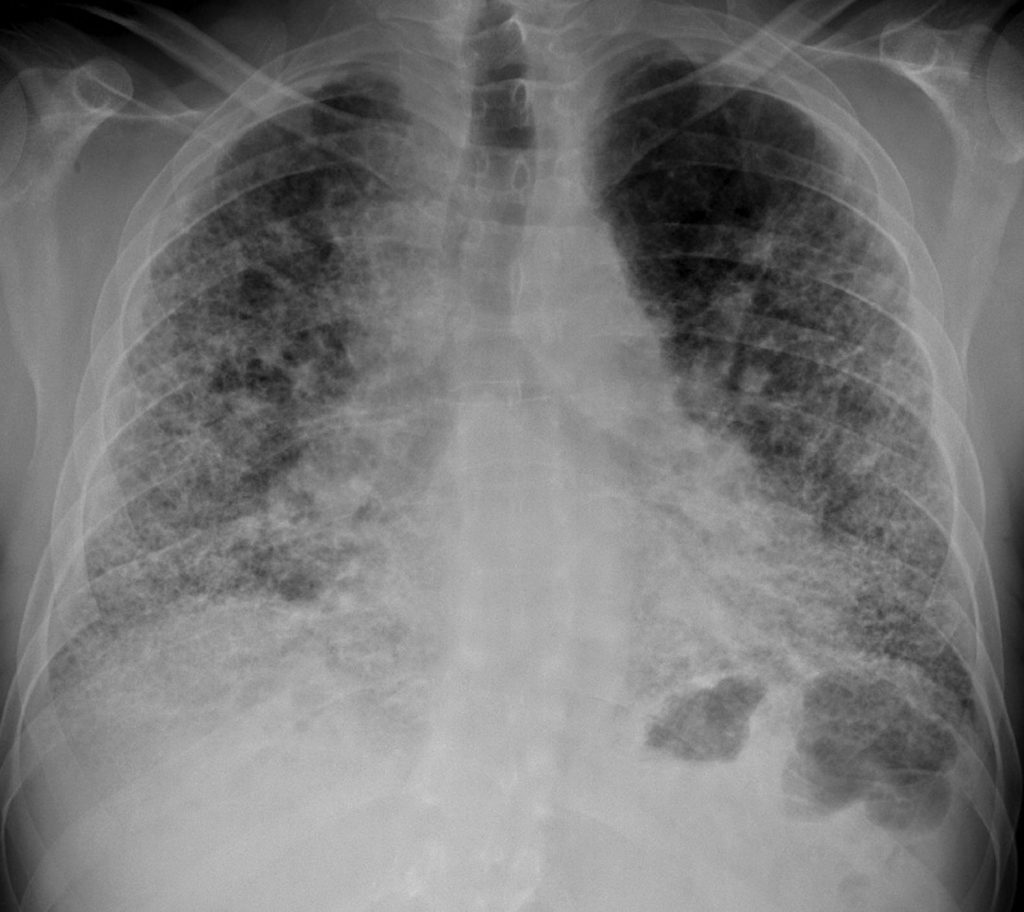

Fig. 97.2. Fibrose pulmonaire idiopathique. Radiographie trois ans après l’établissement du diagnostic.

Opacités diffuses réticulo-nodulaires et diminution de volume des deux poumons.

Source : CERF, CNEBMN, 2022.